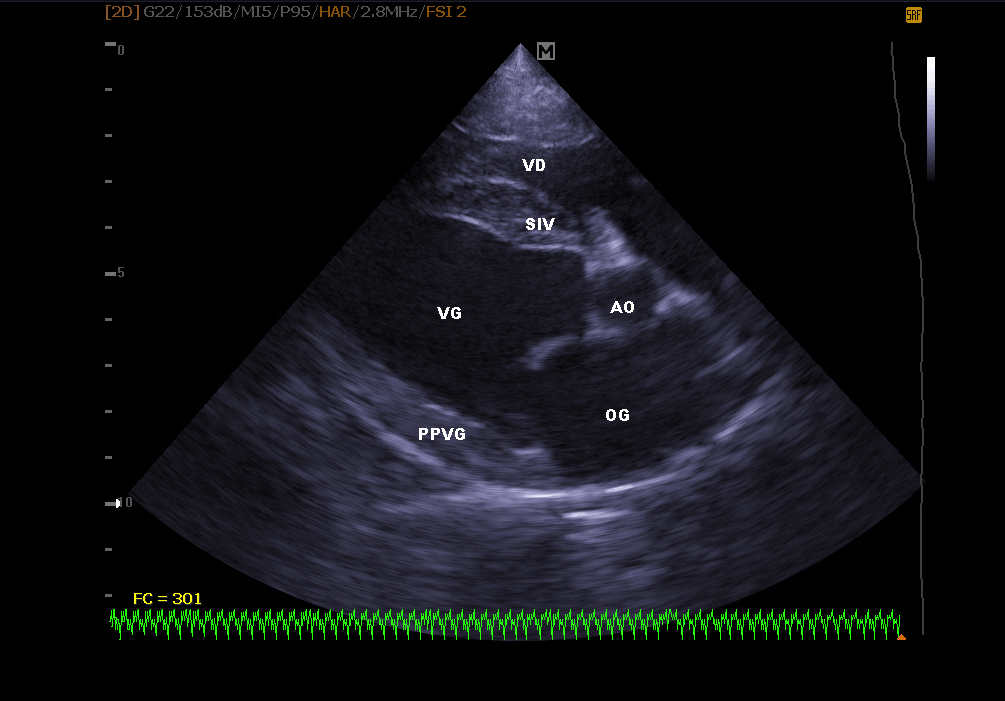

Échographie cardiaque:

Elle permet de visualiser les différentes parties du cœur (parois, cavités, valvules) et de repérer d’éventuelles anomalies qui empêchent un fonctionnement cardiaque correct . En cas d’insuffisance cardiaque, l’échocardiographie permet aussi un suivi régulier de la morphologie cardiaque. Il est alors plus facile de réajuster le traitement mis en place.